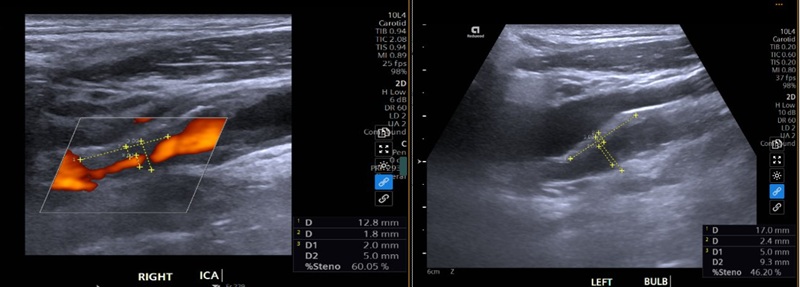

Đáng chú ý, siêu âm động mạch cảnh phát hiện xơ vữa động mạch cảnh hai bên với nhiều vị trí hẹp. Trong đó, động mạch cảnh trong bên phải bị hẹp khoảng 70% do mảng xơ vữa vôi hóa, đây là mức độ hẹp nặng, làm giảm đáng kể lượng máu lên não và tiềm ẩn nguy cơ cao gây đột quỵ. Ngoài ra, xoang cảnh phải hẹp khoảng 50%; bên trái ghi nhận các vị trí hẹp nhẹ đến trung bình.

Hình ảnh siêu âm động mạch cảnh của bệnh nhân phát hiện nhiều vị trí hẹp